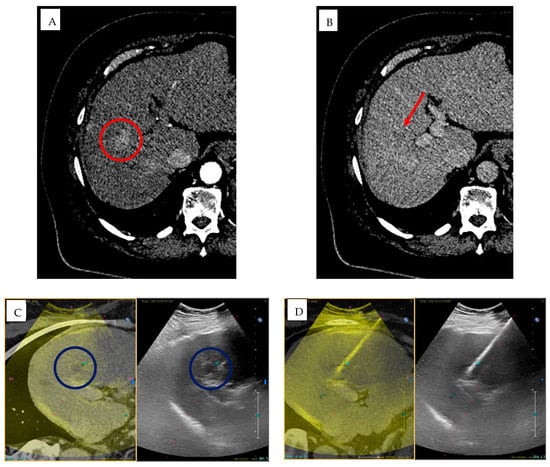

Fusion imaging is a technique based on the integration of different imaging modalities, with the aim to enhance the power of each one, reducing to a minimum the weaknesses of each individual mode. The process consists of different steps. The first step is importation of data from a previous CT/MR/PET exam, followed by the spatial alignment of the imaging dataset and both anatomical landmarks and external markers can be used. Imaging registration can be carried manually by the operator, automatically based on matching common anatomical landmarks, or semi-automatically using a combination of both techniques. When an appropriate alignment is achieved, real-time US and CT/MR/PET images are overlaid on the US monitor, displaying the same plane and moving synchronously together [] (Figure 4 and Figure 5).

Figure 4.

A 72-year-old man with HCC treated with MWTA under fusion imaging guidance. (A) Pre-procedural planning using fusion of CT and ultrasound images to identify the target lesion. (B) Intra-procedural monitoring during insertion of the MWTA antenna into the target lesion. (C,D) Prediction of the ablation zone using XperCT software (EPIQ PercuNav, Philips fusion system) (purple circles).

Figure 5.

A 71-year-old man with HCC in the setting of NASH-related liver disease, previously treated with MWTA under fusion imaging guidance. (A,B) Pre-treatment CT images show a 2 cm lesion in segment VII of the liver, demonstrating arterial phase hyperenhancement (red circle) (A) and venous phase washout (red arrow) (B). (C) Fusion imaging (EPIQ PercuNav, Philips) showing selection of the target lesion (blue circles) in segment VII using ultrasound–CT co-registration. (D) Introduction of the MWTA antenna (20 cm length) into the target lesion; ablation performed for 2 min 30 s at 150 W. (E) Intra-procedural monitoring demonstrates the typical “popcorn effect” of the hepatic parenchyma caused by tissue heating and vaporization. (F,G) Post-treatment CT images in the arterial (F) and venous (G) phases demonstrate a 3 cm hypodense area in segment VII, consistent with complete response at 1-month follow-up.

A major enhancement to CBCT is its integration with image fusion. The alignment between preoperative CT and intraoperative CBCT improves visualization of hepatic lesions and facilitates accurate hepatic segmentation []. Multimodal fusion-guided navigation merges preoperative images with fluoroscopy or CBCT for advanced 3D orientation, aiding in selective chemoembolization, complex biopsies, and vascular malformation treatments [,,]. By improving targeting, fusion technologies can also reduce procedural time, lowering radiation exposure for both patients and operators [].

Modern systems now offer automatic, dynamic registration, aligning pre- and intraoperative datasets without manual intervention and ensuring smooth transitions between modalities []. The clinical applications of CBCT and image fusion are extensive. In liver oncology, this combination is becoming the emerging standard for TACE and ablation procedures, allowing precise targeting of lesions that are difficult to visualize with a single modality [,,]. In vascular interventions, CBCT with vascular overlay improves embolization planning and stent placement in complex anatomies []. Nonetheless, there are limitations and considerations. CBCT is susceptible to motion artifacts, particularly in non-cooperative patients, and involves higher radiation doses than ultrasound—though lower than conventional CT []. Image fusion accuracy heavily depends on precise registration; even small errors can affect targeting. Finally, proper use of CBCT and fusion systems requires specialized training and significant financial investment, which may be challenging for smaller healthcare facilities.